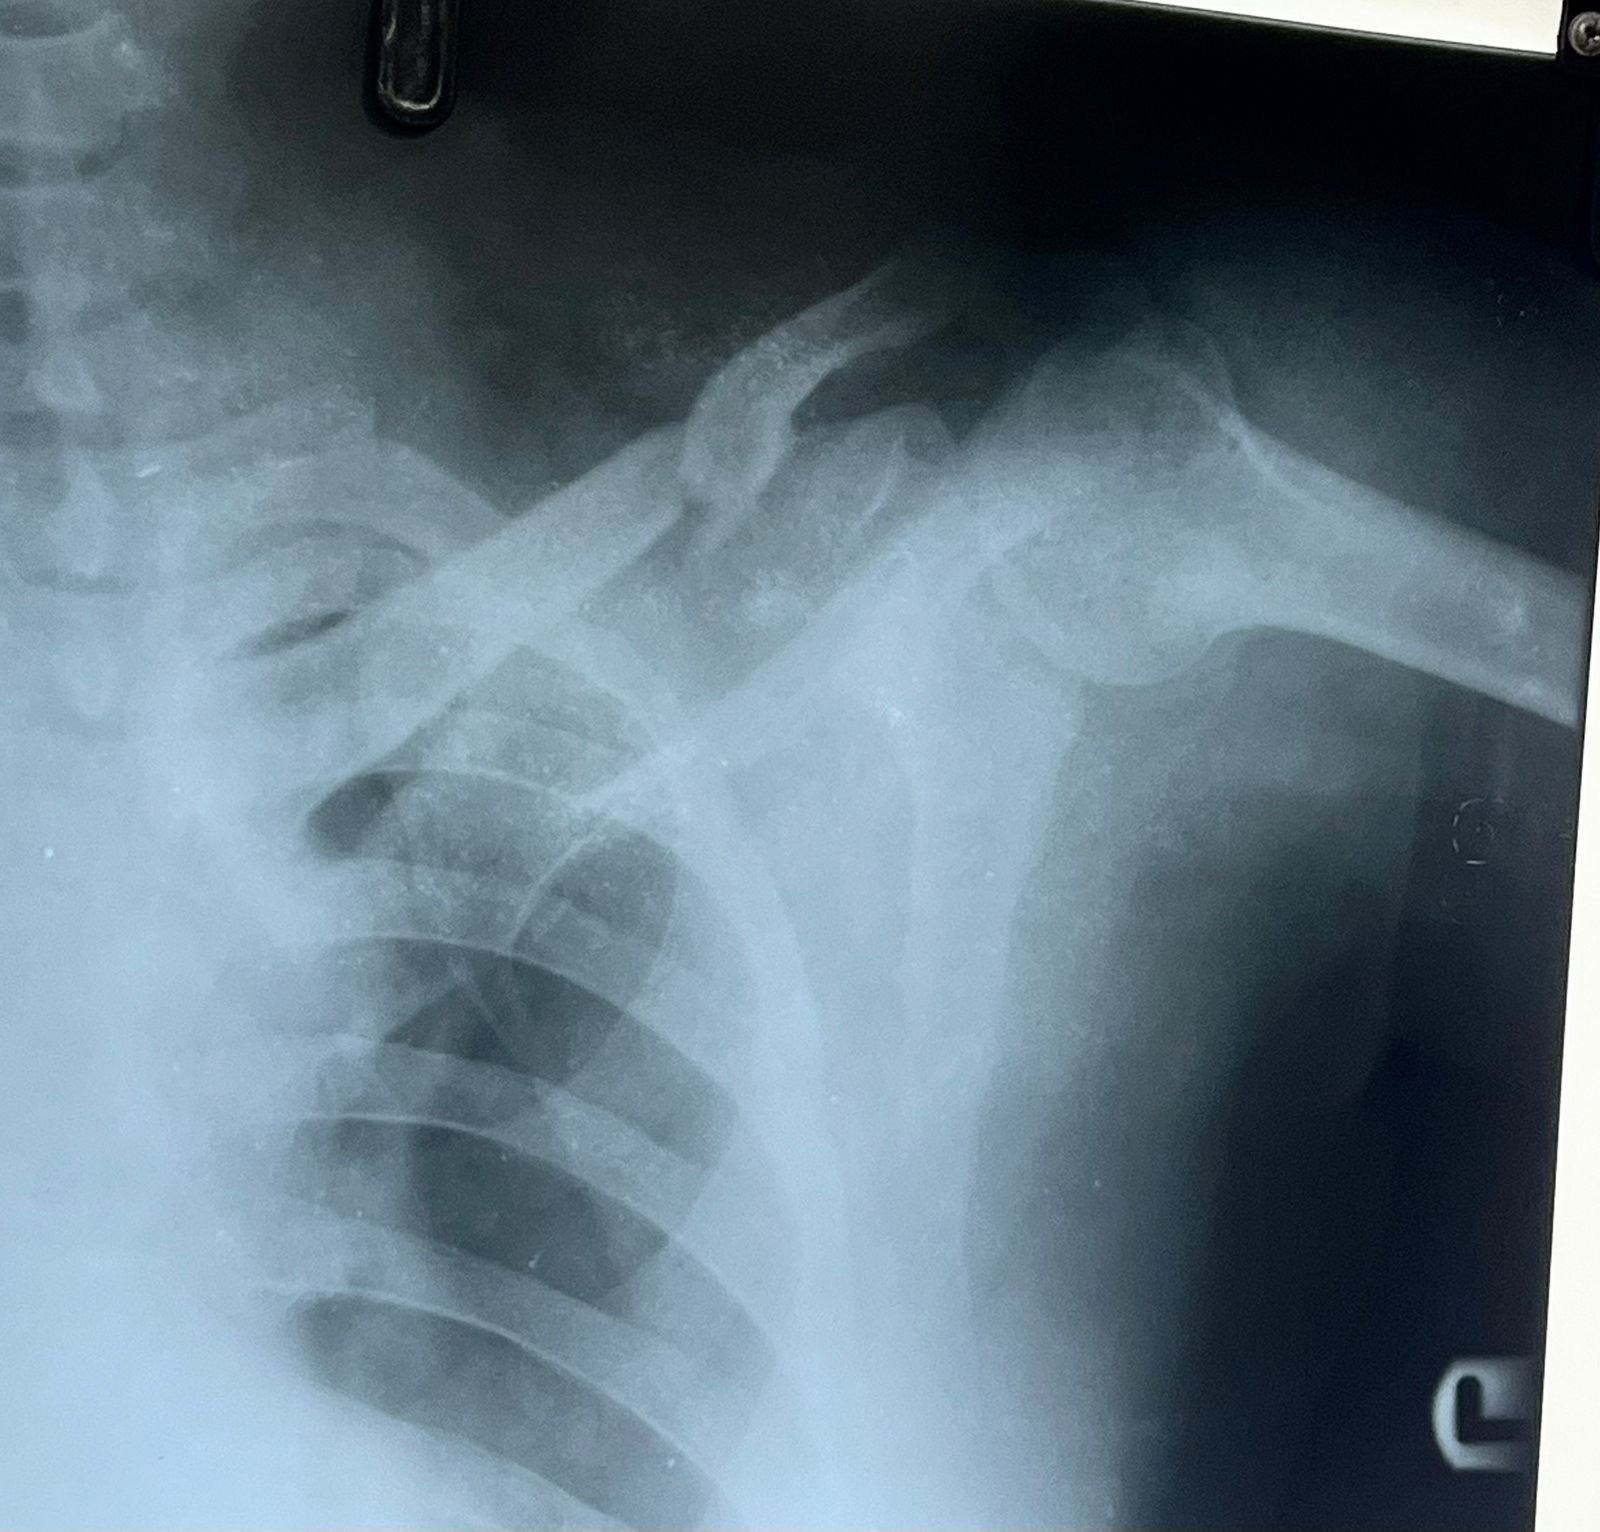

& fibula | Heal fracture pre & postop | Clavicle

fracture pre &

Heal fracture pre & postop | Clavicle fracture pre &

postop | Congenital foot deformity pre & post